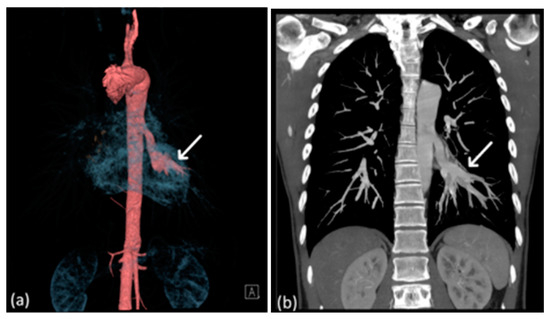

A 51-year-old male patient with no significant medical comorbidities was incidentally discovered to possess a retrocardiac mass after undergoing a chest radiography (Figure 1) during a routine health assessment. Despite the absence of symptoms such as pyrexia, cough, dyspnea, or hemoptysis, the initial impression leaned toward a primary pulmonary neoplasm localized within the left lower lung. Subsequent examinations through CTA (64-slice detector, GE Lightspeed VCT) revealed an enlarged anomalous pulmonary artery originating from the descending thoracic aorta (Figure 2b). Remarkably, the bronchopulmonary distribution within the lung parenchyma remained within normal limits (Figure 2c). As indicated by CTA images, venous drainage returned to the left atrium, and the bronchopulmonary connection was anatomically intact.

Figure 2.

(a) Lesion in the retrocardiac area mimicking lung mass in the non-contrast CT study (arrow). (b) Aberrant systemic artery (arrow) originating from the thoracic aorta (curve arrow), supplying the left lower lung, as revealed by CTA; the bronchovascular marking of the left lower lobe is prominent in the lung window of the CTA (arrowhead). (c) CT volume rendering indicating the continuity of the bronchogram from caudal to cranial; the bronchopulmonary tract is patent and continuously (arrowhead) connected to the main bronchus in volumetric rendering of the caudal-cranial view.